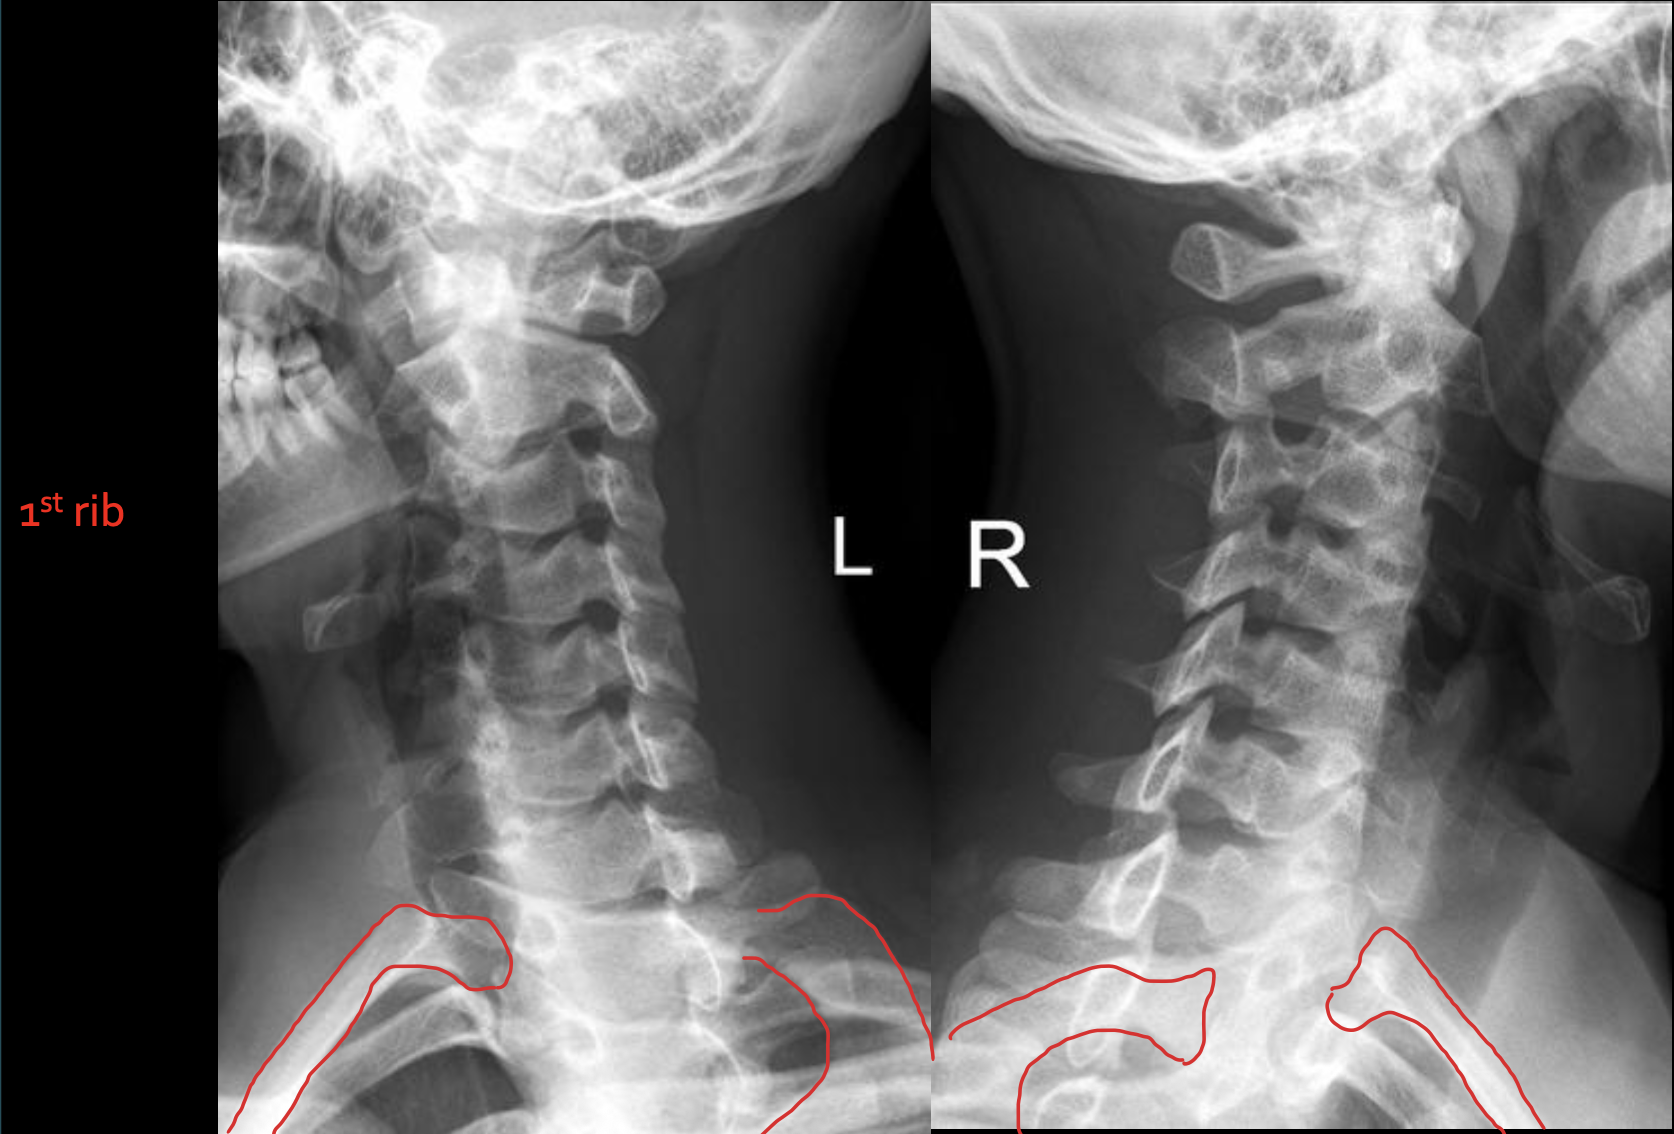

1st rib

T1